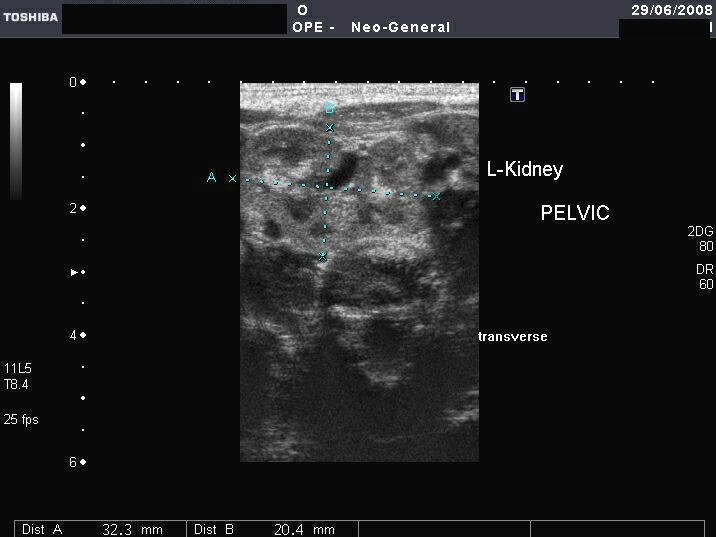

This female neonate presented with imperforate anus. Sonography reveals normally located right kidney. However the left kidney is not visualized in left renal fossa. Ultrasound images reveal a pelvic kidney that appears somewhat rounded, located posterior and superior to the bladder. The renal pyramids of both kidneys appear echogenic suggestive of early nephrocalcinosis. The uterus of this neonate was not visualized well. Color doppler imaging shows the vascularity of the pelvic kidney. Images taken using a Toshiba Xario machine.